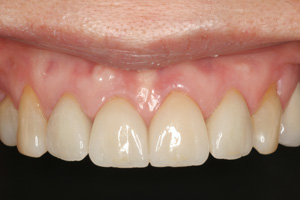

Clinical Cases